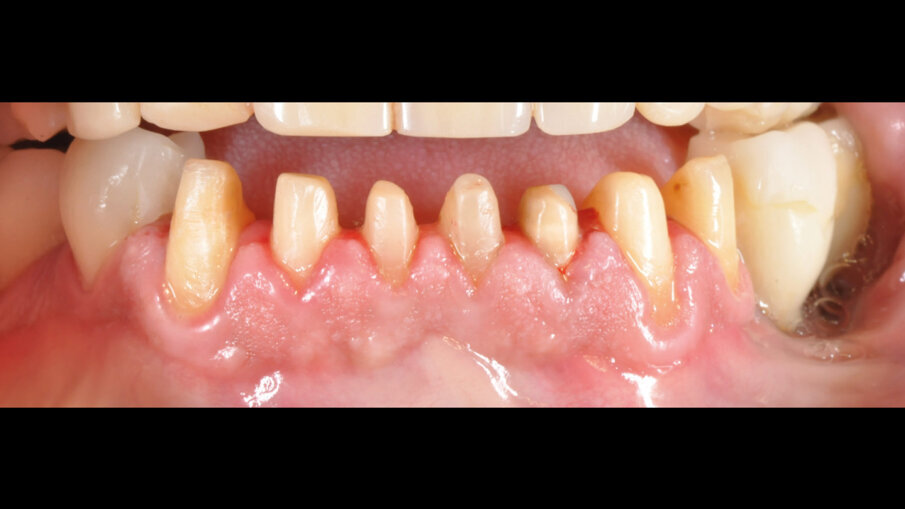

Il paziente lamentava l’aspetto estetico e la riduzione della capacità masticatoria, sottolineando l’impossibilità di affrontare molteplici visite di riabilitazione protesica (Fig. 1). Si è proceduto con una seduta di igiene orale approfondita, esami radiografici endorali e una scansione intraorale per registrare in dettaglio lo stato iniziale del paziente. Successivamente, sono state rimosse le lesioni cariose dagli elementi affetti, gravemente compromessi ma recuperabili (Fig. 2). È stato proposto al paziente un trattamento chairside in grado di risolvere i problemi funzionali ed estetici in poche ore, utilizzando preparazioni minimamente invasive e la tecnica di stampa dei restauri eseguita direttamente in studio. Dopo l’accettazione del paziente, sono state effettuate preparazioni mini-invasive, levigate e lucidate con strumenti abrasivi siliconici a grana decrescente (media/fine). Ultimate le preparazioni e verificate le condizioni dei tessuti molli e la visibilità dei margini cervicali, si è proceduto con la scansione intraorale delle arcate e la registrazione dei rapporti occlusali (Fig. 3).

Figg. 2, 3_Preparazione gruppo frontale da 33 a 43.